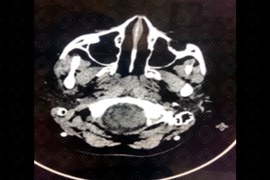

Descrição das imagens: Tomografia computadorizada do plano axial, exibindo a fossa posterior pequena e interdigitação da foice cerebral. Achados compatíveis com malformação de Chiari tipo 2. Observa-se ainda a presença de cateter de derivação ventricular na região parietal posterior esquerda.

• Tomografia computadorizada do crânio: Fossa posterior obliterada (pequena), incisura do tentório alargada, mesencéfalo em bico e deslocamento inferior do vérmis cerebelar;